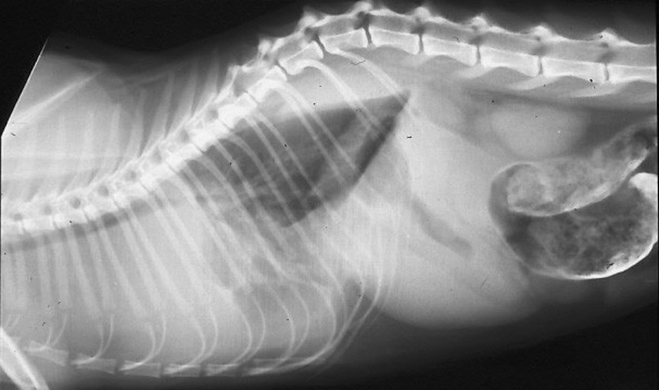

What are the signs of left sided CHF (pulmonary oedema)?

Tachypnoea, both inspiratory and expiratory, restrictive breathing pattern

Cough in dogs due to left atrial enlargement

+/- soft inspiratory crackles on auscultation (don't rely on this - not present with bad oedema)